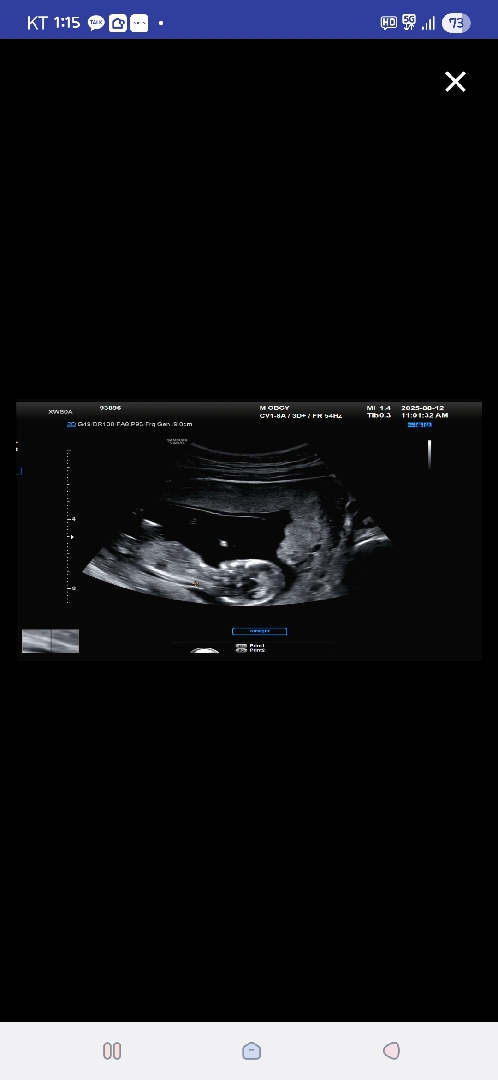

1차기형아검사 하고왔어요!

손뀨락 5개확인 목투명대합격 ! 피검사하구 2차 때검사하고 통합적으로 결과 알려주신다는데 아직까지는 괜찮다고 하셨어오 다행이에여 ㅠㅠ 성별은 한달뒤에 알수있다고 하는데 언능 시간이 흘렸으면 좋겠어요 ㅎㅎ